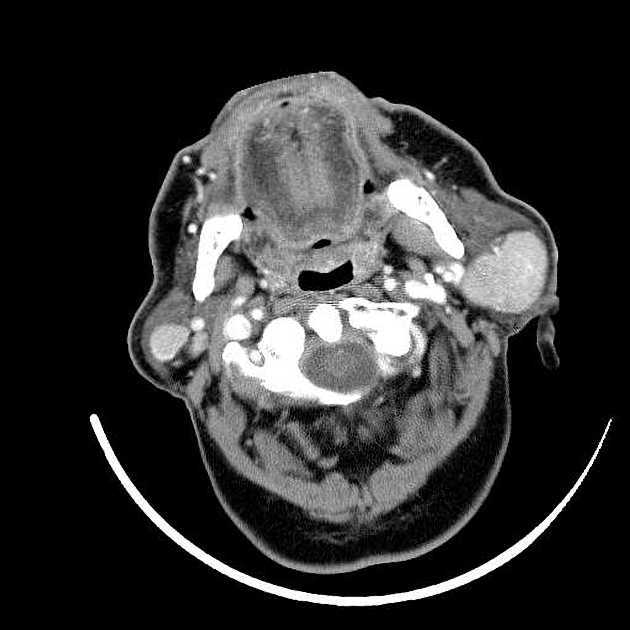

Spinal DAVF will have no flow voids in the cord itself, with have funky serpentine vessels surrounding the cord

spinal avm

notice the flow voids in the spiral cord. Spinal DAVF will have no flow voids in the cord itself, with have funky serpentine vessels surrounding the cord